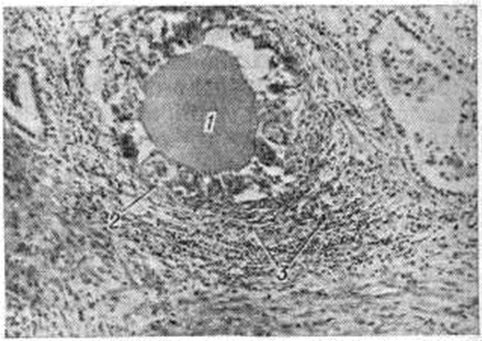

Рис. 1.

Микропрепарат щитовидной железы при подостром тиреоидите: 1 — коллоид, излившийся из фолликула в строму; 2 — гигантская клетка; 3 — лимфоплазмоцитарная инфильтрация стромы; окраска гематоксилин-эозином; ×70.

В течении подострого Тиреоидит в зависимости от содержания в крови тиреоидных гормонов выделяют несколько стадий. В I стадии подострого Тиреоидит в результате нарушения целостности мембран тиреоцитов и фолликулов щитовидной железы и выхода их содержимого в строму железы в крови повышается концентрация тироксина (смотри полный свод знаний) — Т4 и трийодтиронина (смотри полный свод знаний) — Т3, а также негормональных соединений йода, что увеличивает разницу между количеством белково-связанного йода (смотри полный свод знаний) и бутанолэкстрагируемого йода (смотри полный свод знаний) и блокирует захват йода щитовидной железой. Строма щитовидной железы инфильтрирована сегментоядерными лейкоцитами, лимфоцитами и тканевыми макрофагами. У некоторых больных в крови появляются антитиреоидные антитела. Во II стадии происходит снижение интенсивности деструктивных процессов в щитовидной железе, что ведёт к уменьшению концентрации негормональных соединений йода в крови и восстановлению механизма захвата йода железой. В строме железы отмечается скудная инфильтрация макрофагами и лимфоцитами с примесью плазматических клеток и исчезновение нейтрофилов. Массы излившегося в строму из разрушенных фолликулов коллоида окружены гистиоцитами и гигантскими клетками (смотри полный свод знаний), сходными с так называемый клетками инородных тел (рисунок 1). Для III стадии в связи с уменьшением объёма функционирующей железистой ткани характерны понижение содержания в крови тиреоидных гормонов и иногда транзиторный гипотиреоз. В этой стадии воспалительный процесс стихает, выявляются очаги регенерации фолликулов. В IV стадии — стадии выздоровления — нередко отмечается повышенный захват йода железой, которая прежде была обеднена им, поэтому данное явление носит компенсаторный характер. В то же время содержание Т3 и Т4 в крови снижено или находится в норме. При электронно-микроскопическом исследовании щитовидной железы у больных подострым тиреоидитом III —IV стадии отмечают признаки повышения функциональной активности тиреоцитов, но апикальных псевдоподий, содержащих капли коллоида, нет, а гигантские клетки мезенхимного происхождения представляют собой группы гистиоцитов без признаков фагоцитоза частиц коллоида. В конце стадии выздоровления все показатели нормализуются.